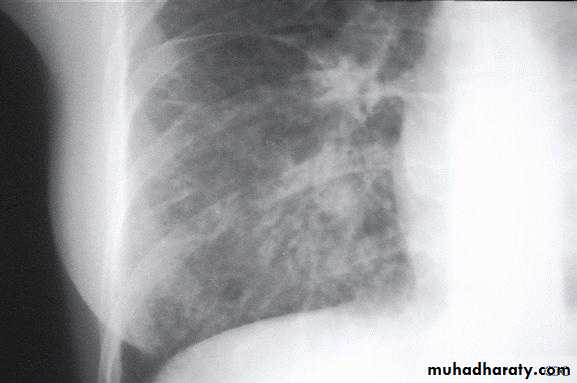

Coexistent debilitating illness and often preceded by influenza. Radiographic features include multilobar shadowing, cavitation, pneumatoceles and abscesses. Dissemination to other organs may cause osteomyelitis, endocarditis or brain abscesses. Mortality up to 30%.

Chest X-ray show multiple lung abscess

Staphylococcus pneumonia

• Staph. Aureus: Suggested by multilobar shadowing, cavitation, pneumatocoeles and abscesses